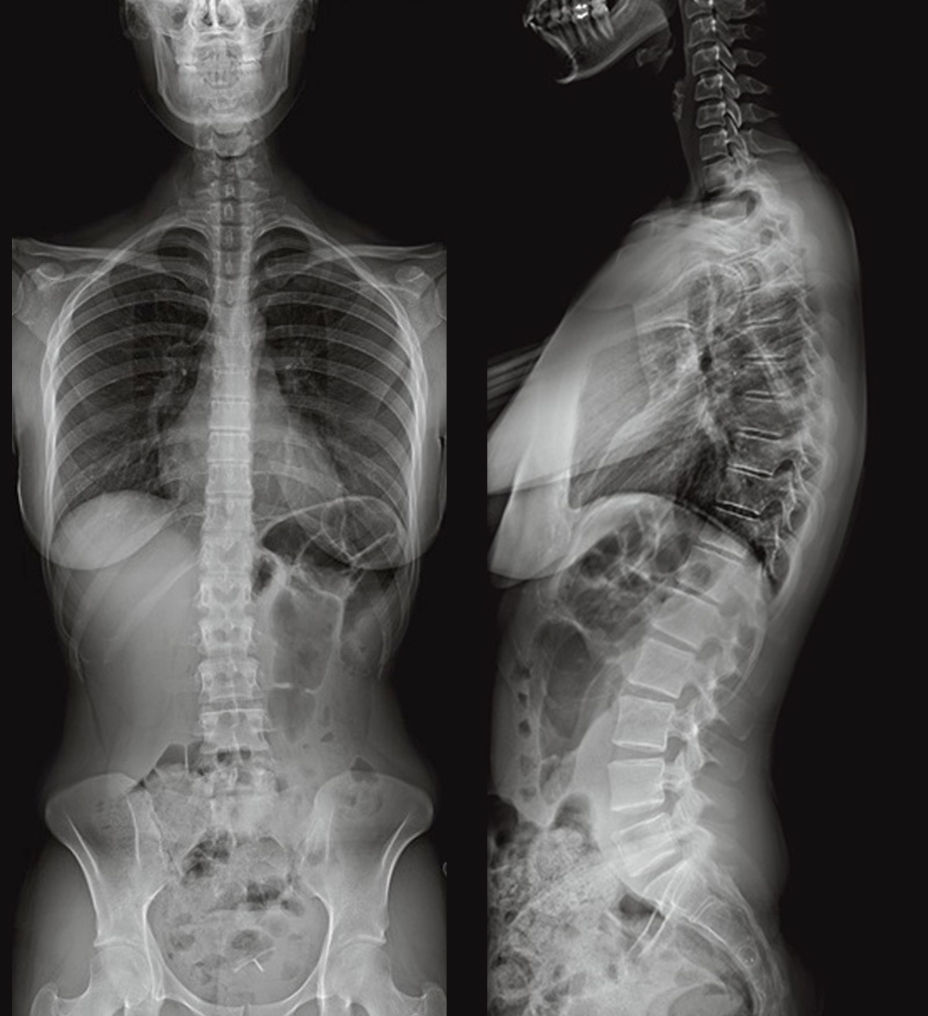

Minimized image variability improves diagnostic confidence

The Definium Pace Select ET uses high-quality detectors and AI-powered advanced image processing software to reduce variability and provide optimal image quality, with the clarity, contrast and resolution to make decisive decisions.

These dose-efficient, high DQE wireless detectors enable visualization of extraordinary anatomical detail, offering 4x higher resolution than 200 micron pixel detectors.

Helix™ 3.0 advanced image processing provides outstanding clarity and exceptional anatomical detail across image types with anatomy-specific image enhancement.

Helix 3.0 algorithms are designed to deliver outstanding resolution, excellent edge presentation, consistency and noise handling. Algorithms include: